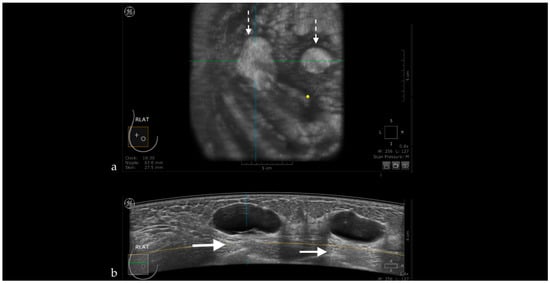

Figure 5. The case of a bulging cyst visible on both coronal (a) and axial planes (b) at 2.30 o’clock, 25.6 mm from the nipple (yellow dot). Due to the superficial location of the lesion, the transducer slides over its edge producing the skip artifact seen on the coronal plane (white dotted arrow).

Nipple Artifact